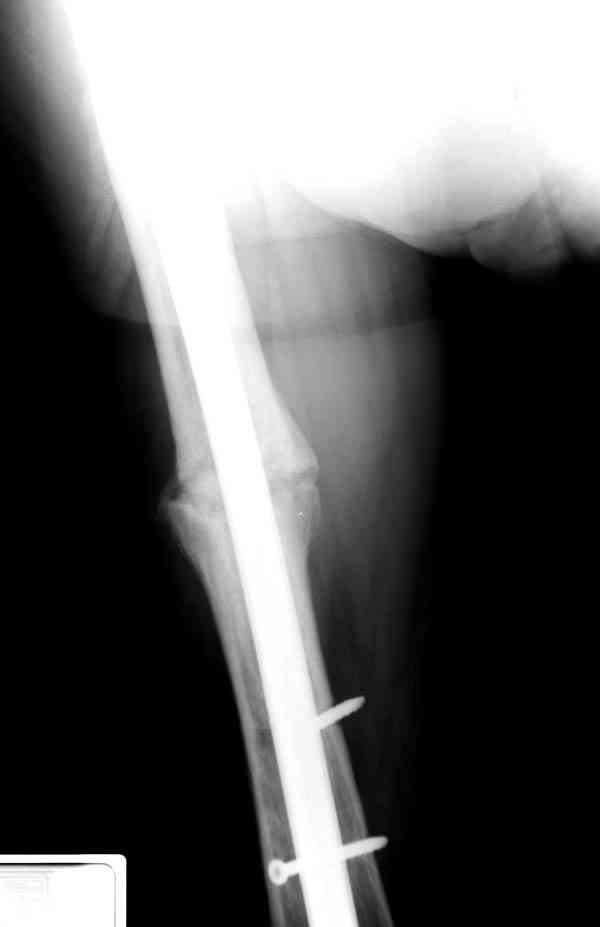

Сросшаяся малоберцовая как распорка привела к образованию ложного

сустава. В таких случаях удаляем сломанный штифт и проводим

стимуляцию ложного сустава рассверливанием. Рассверливание канала

создает стимуляцию на месте ложного сустава, и динамический вариант

блокировки штифта с большим диаметром создаст стабильность. Ранняя

нагрузка после остеотомии малоберцовой приведет к сращению ложного

сустава.